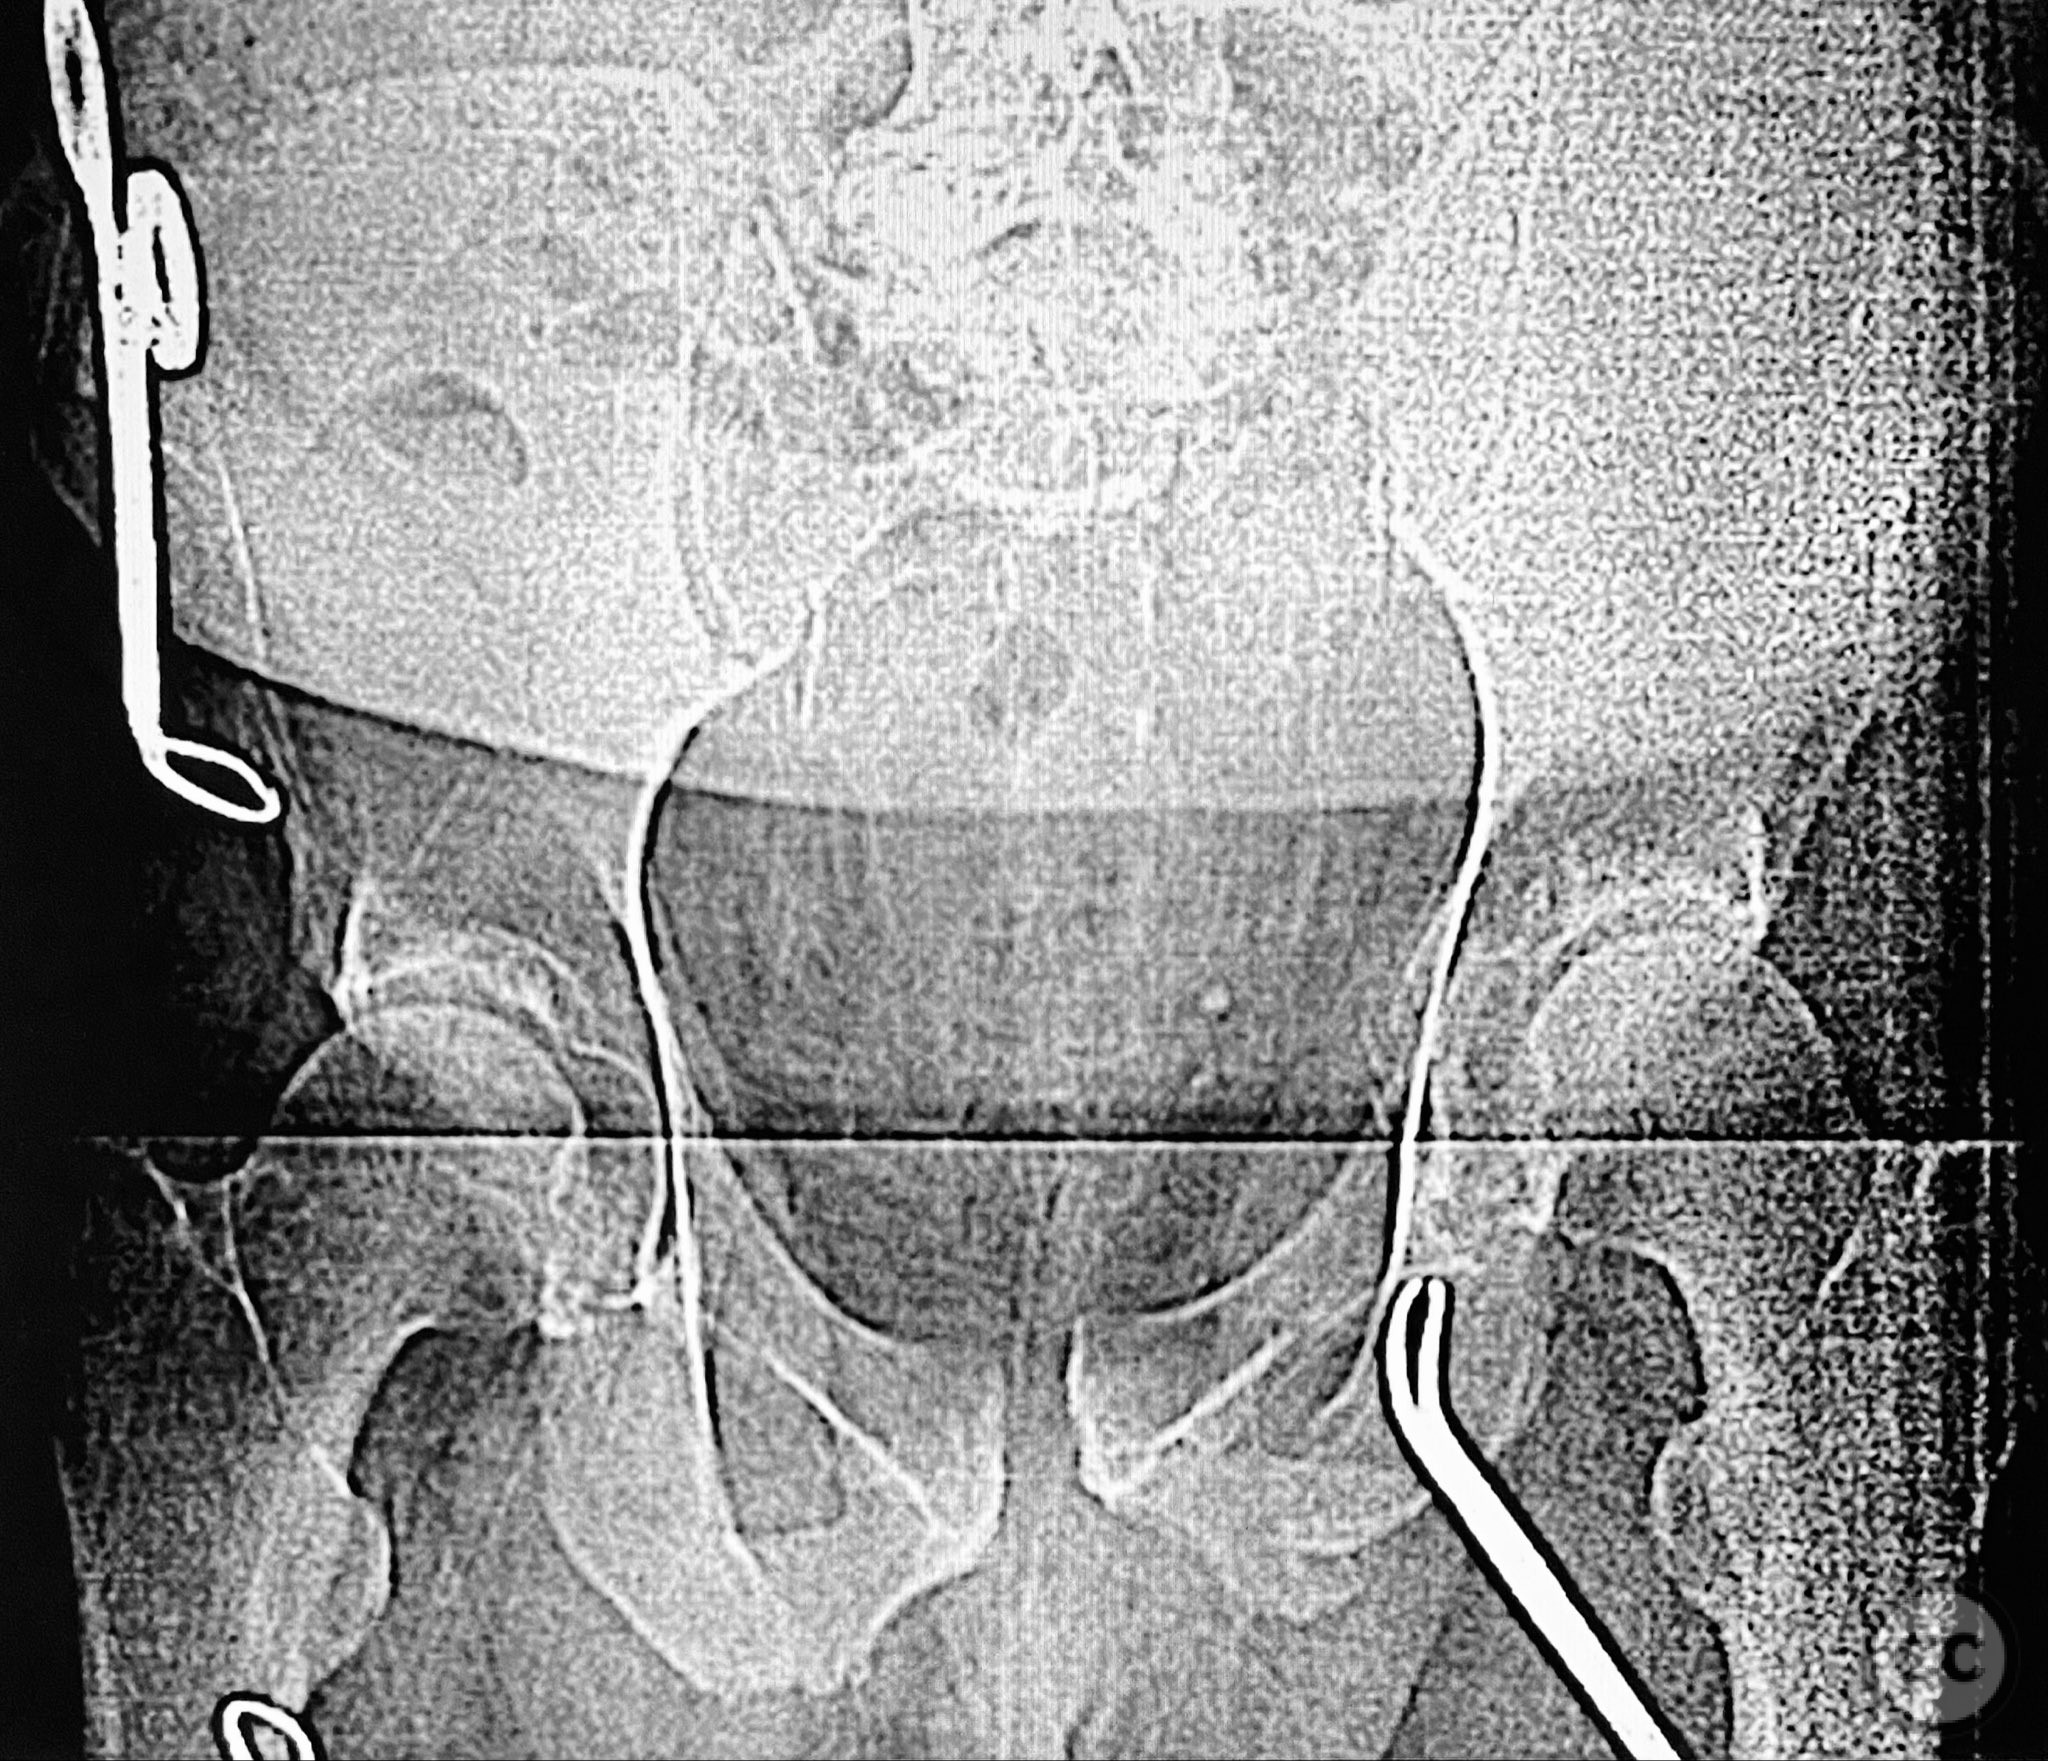

Clinical and radiological findings:  Middle-aged male with a high-energy pelvic ring injury, presenting with significant pain and mechanical instability. Initial radiographs demonstrated comminution and displacement of the posterior pelvic ring, including sacral fractures and disruption of the anterior ring at the pubic symphysis and rami. Application of a circumferential pelvic sheet provided partial reduction and improved comfort. No neurovascular deficits were noted. CT imaging confirmed a comminuted sacral fracture (AO/OTA 61-C1.3), with bilateral pubic rami fractures and symphyseal diastasis. The posterior elements demonstrated both vertical and rotational instability.

Planning remarks:  The preoperative plan involved staged management: initial prone positioning for open reduction and internal fixation (ORIF) of the sacrum, utilizing the dorsal cortical fracture edges for direct reduction and clamping, followed by percutaneous iliosacral screw fixation and a posterior transiliac screw. Definitive anterior ring stabilization was planned subsequently via open reduction and internal fixation of the symphysis and pubic rami through an anterior approach.

Anatomical surgical approach:  Posterior approach to the sacrum via a midline longitudinal incision, subperiosteal dissection to expose the dorsal sacral cortex and fracture lines. Direct reduction of the sacral fragments using clamps applied to the dorsal cortical edges, with intraoperative fluoroscopic guidance. Placement of iliosacral screws (non-cannulated, <130mm length due to implant availability at the time) across S1, supplemented by a posterior transiliac screw. For anterior fixation, a Pfannenstiel incision was used to expose the symphysis pubis and superior pubic rami; reduction achieved with pointed reduction forceps, followed by plate osteosynthesis of the symphysis and screw fixation of the rami as indicated.